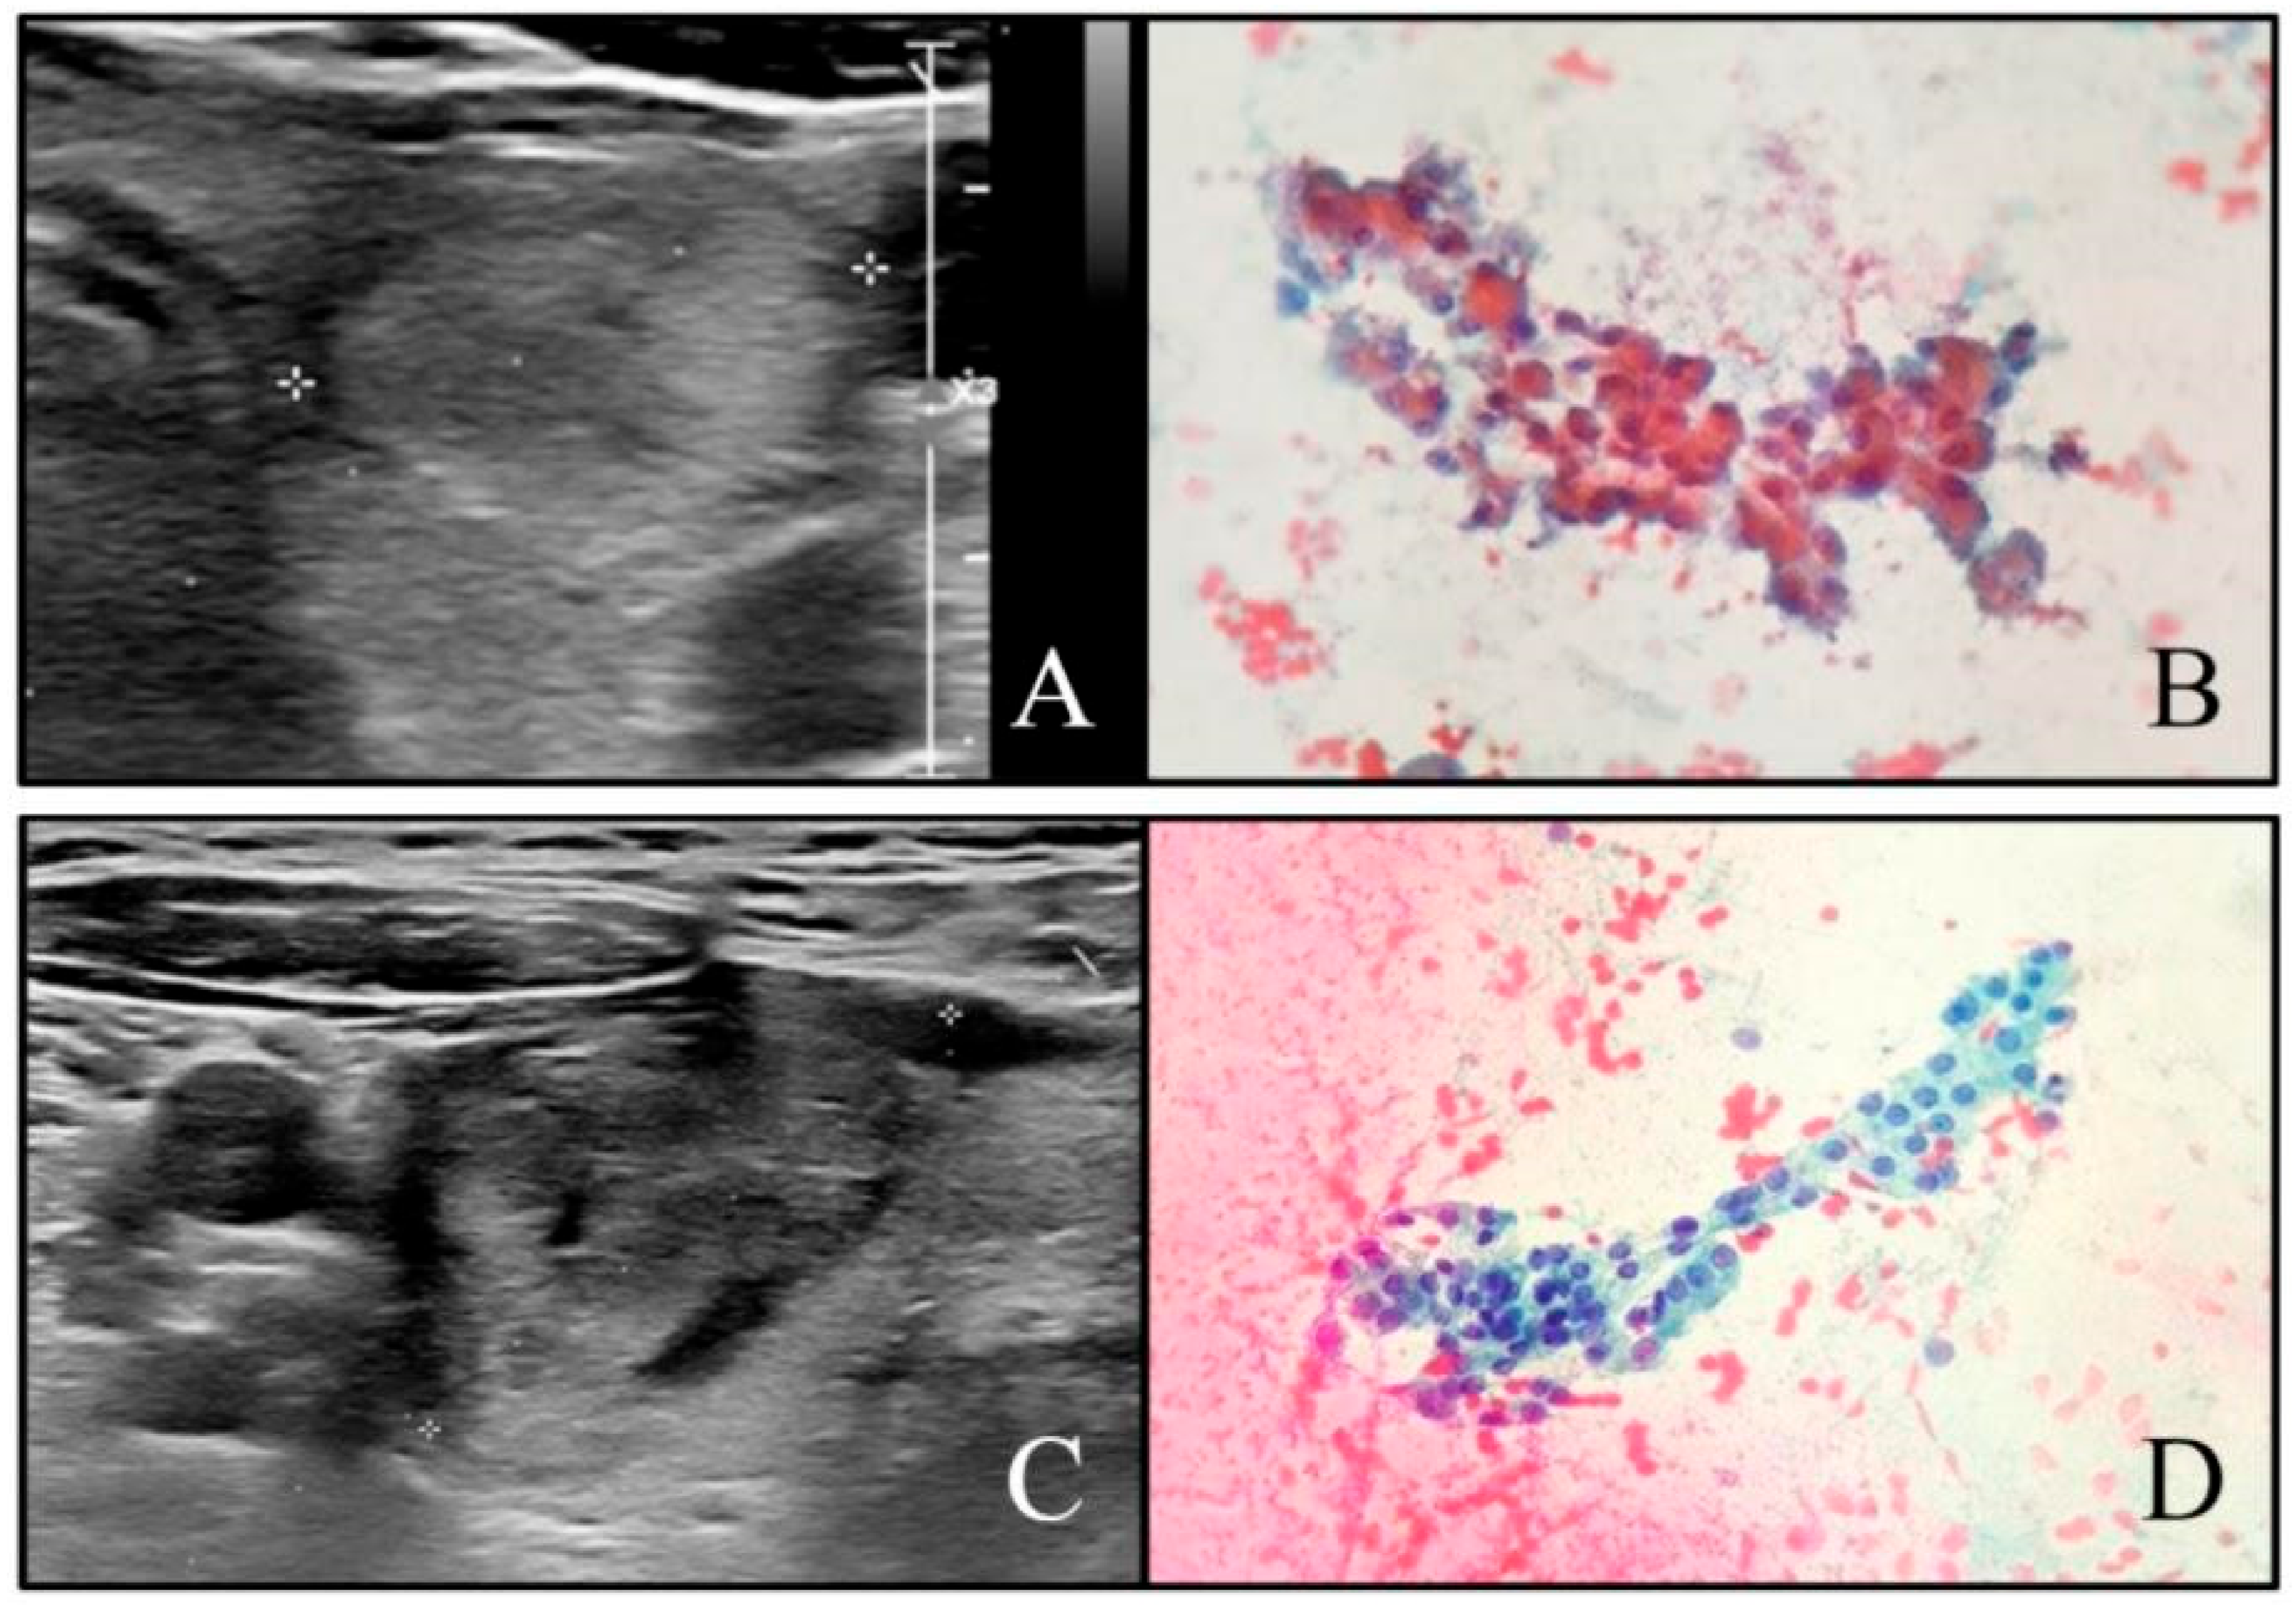

2.2. Ultrasound Evaluation

2.3. Cytopathology and Histopathology